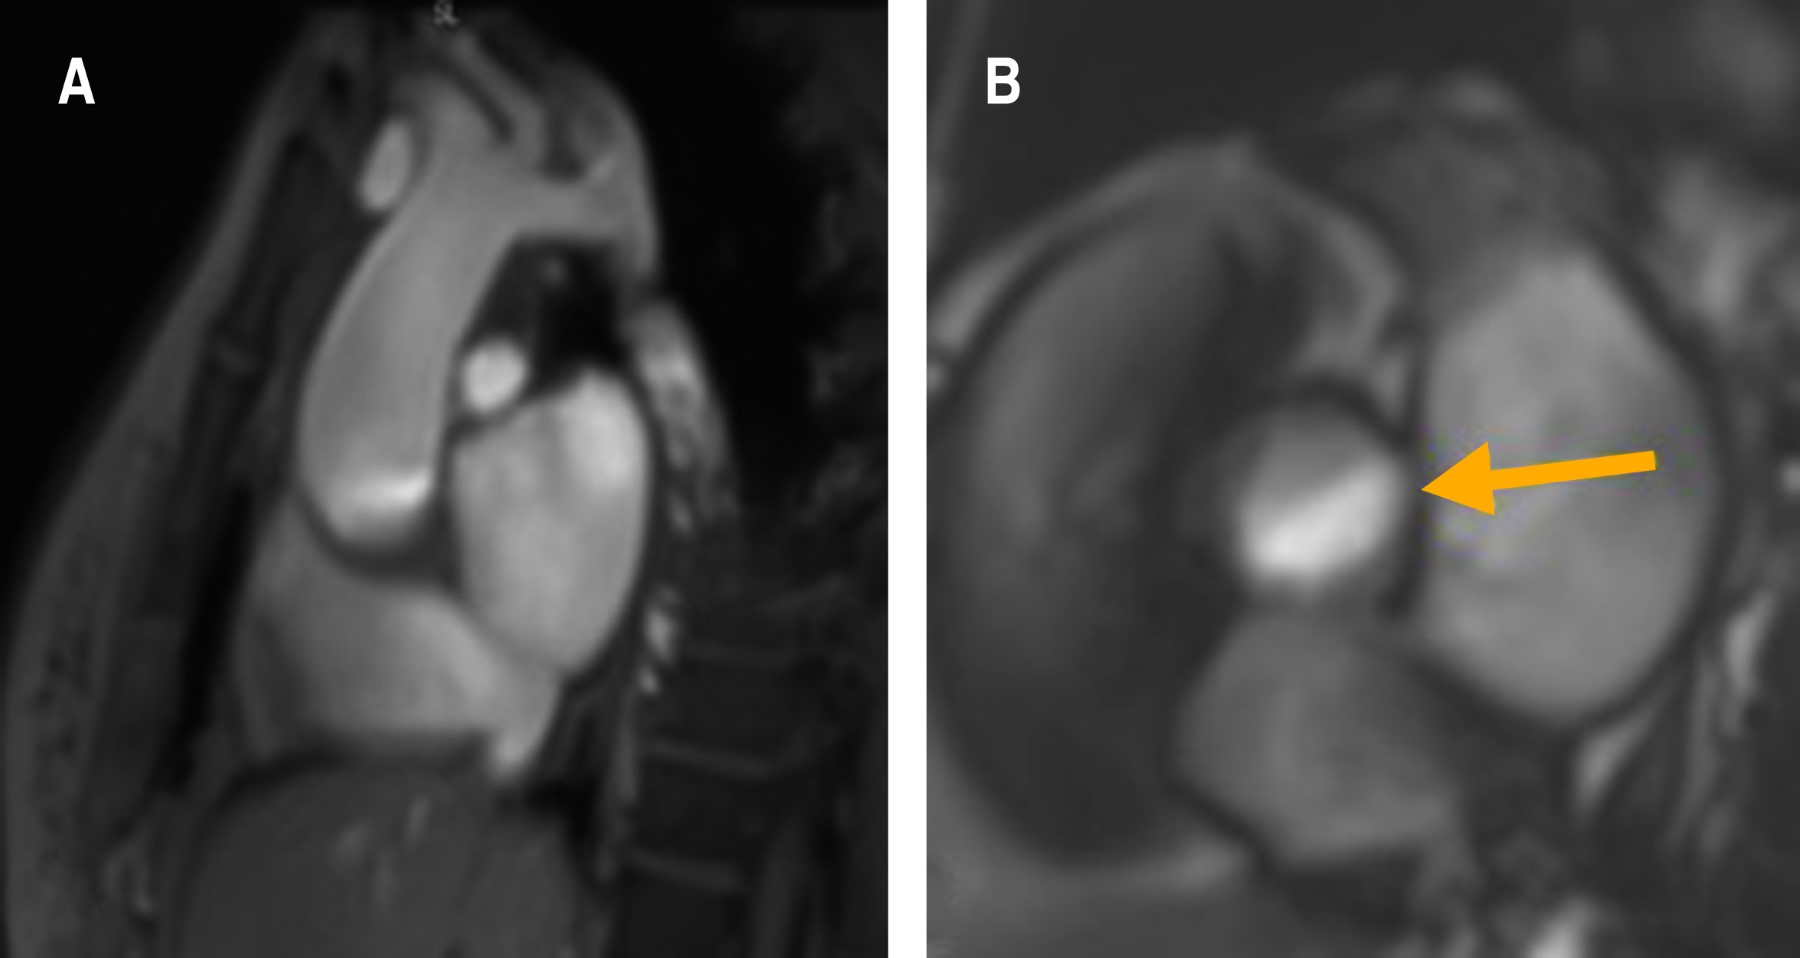

Las cardiopatías congénitas en México ocupan el segundo lugar de malformaciones congénitas en los recién nacidos, con una incidencia de 0.8-1.4%. El doble orificio de la válvula mitral (DOVM) es una cardiopatía congénita rara, con una incidencia reportada de 0.05%. Esta malformación consiste en la presentación anatómica de dos orificios mitrales comúnmente asociada a otras malformaciones congénitas como defectos septales, malformaciones completas o parciales del canal atrioventricular, coartación aórtica, tetralogía de Fallot, comunicación interauricular o interventricular, anomalía de Ebstein y persistencia del conducto arterioso. Las características clínicas son variables e incluso pueden pasar desapercibidas y ser diagnosticadas hasta la edad adulta. Se presenta el caso de una mujer joven el cual se encuentra asintomática con diagnóstico de hipertensión arterial, que durante una revisión de rutina fue diagnosticada con múltiples cardiopatías congénitas, de las cuales, su relación está poco descrita en la literatura, siendo este el tercer caso reportado. En la actualidad las técnicas de imagen multimodal permiten la mayor caracterización de las lesiones tanto de la valva como del aparato valvular, con la intención de realizar un abordaje diagnóstico y terapéutico integral para ofrecer el mayor beneficio al paciente.

Figura 3